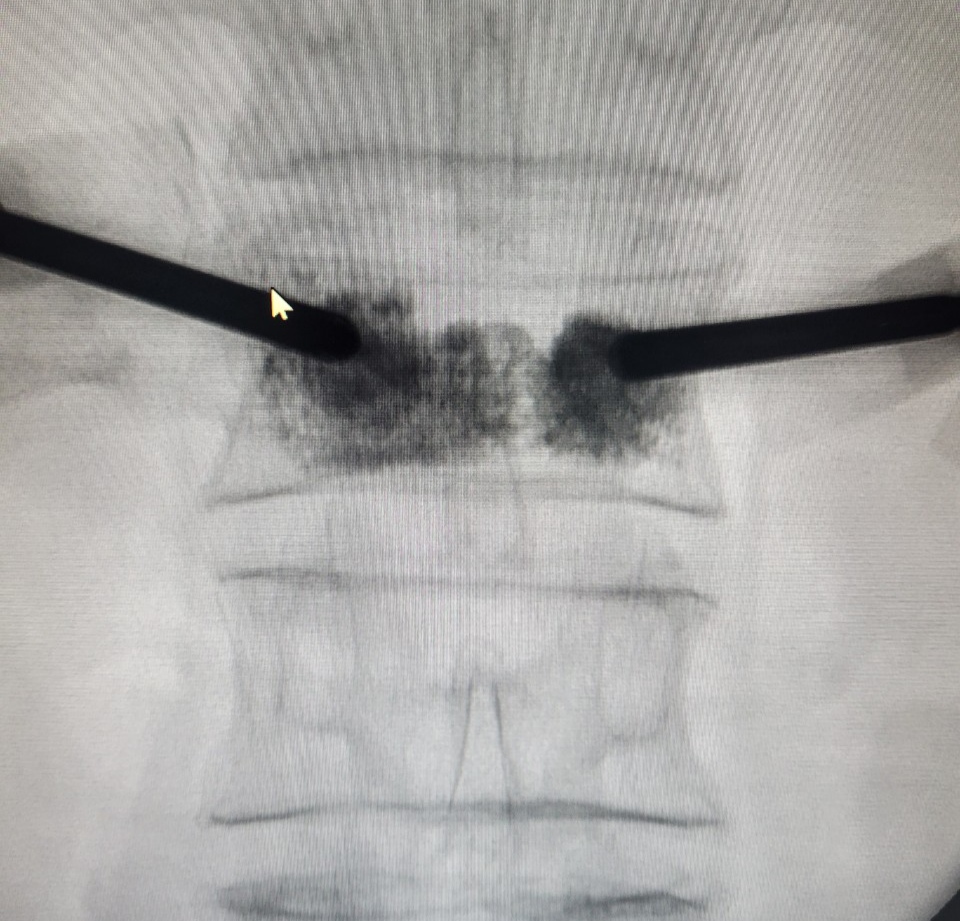

Hình ảnh bơm xi măng sinh học có bóng dưới hướng dẫn của máy C-arm của bệnh nhân S.

Sau gần 30 phút can thiệp, bệnh nhân đỡ đau cột sống thắt lưng, xoay trở tư thế cột sống tốt hơn, có thể đi lại được sau 8 tiếng can thiệp và xuất viện sau đó 3 ngày.